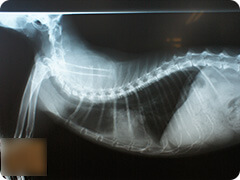

脱臼・関節炎・骨折・骨肉腫など関節液検査やX線検査でわかる骨や関節疾患

- 股関節脱臼

- 事故や先天的な股関節形成不全に付随して脱臼することがあります。

脱臼した側の後ろ足を拳上させ、3本足で歩くようになります。